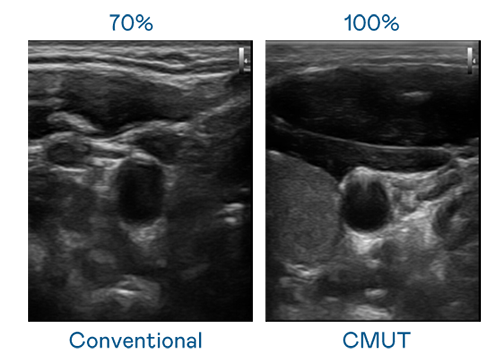

CMUT 技術是一種用電容式微機電元件來產生超音波訊號的技術。與傳統 PZT 壓電式技術相比,CMUT 頻寬增加 30%,更寬頻的超音波訊號讓影像解析度大幅提升,是實現高影像品質醫療超音波掃描、促進精準醫療發展的關鍵技術。

大頻寬帶來超清晰影像

超音波影像的解析度高低,首先取決於探頭能發出的訊號頻寬。asiagame CMUT 可提供高清晰的超音波訊號,提供高頻寬、高靈敏度、影像紋理細節更高的超音波影像,協助醫護人員縮短影像判讀時間及利用精準的醫療影像進行診斷。